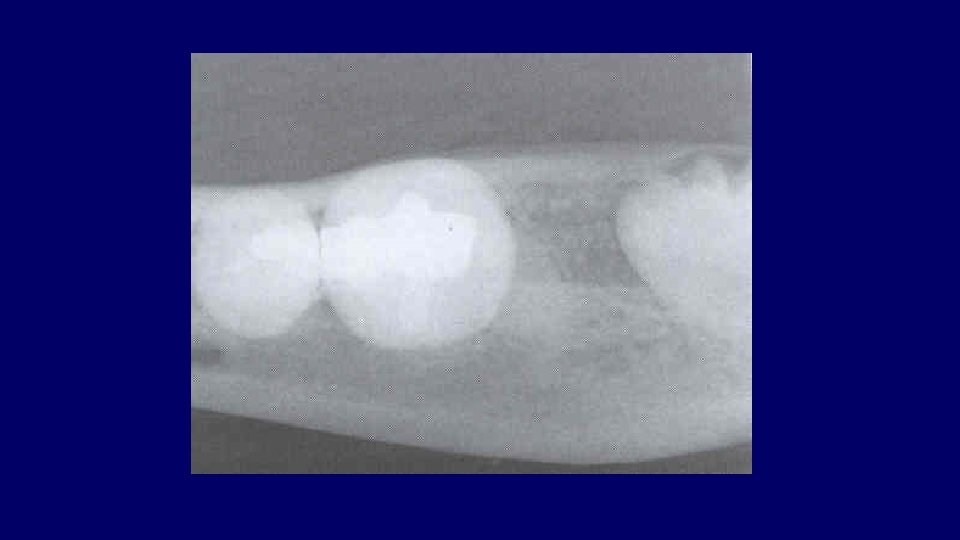

Pell & Gregory Classification • Based on the amount of tooth covered by the anterior border of the ramus • The depth of the impaction relative to the adjacent tooth

Pell & Gregory • Relation to the Ramus Class III

Pell & Gregory • Depth of Impaction – Mandibular Class A Class B Class C

Pell & Gregory